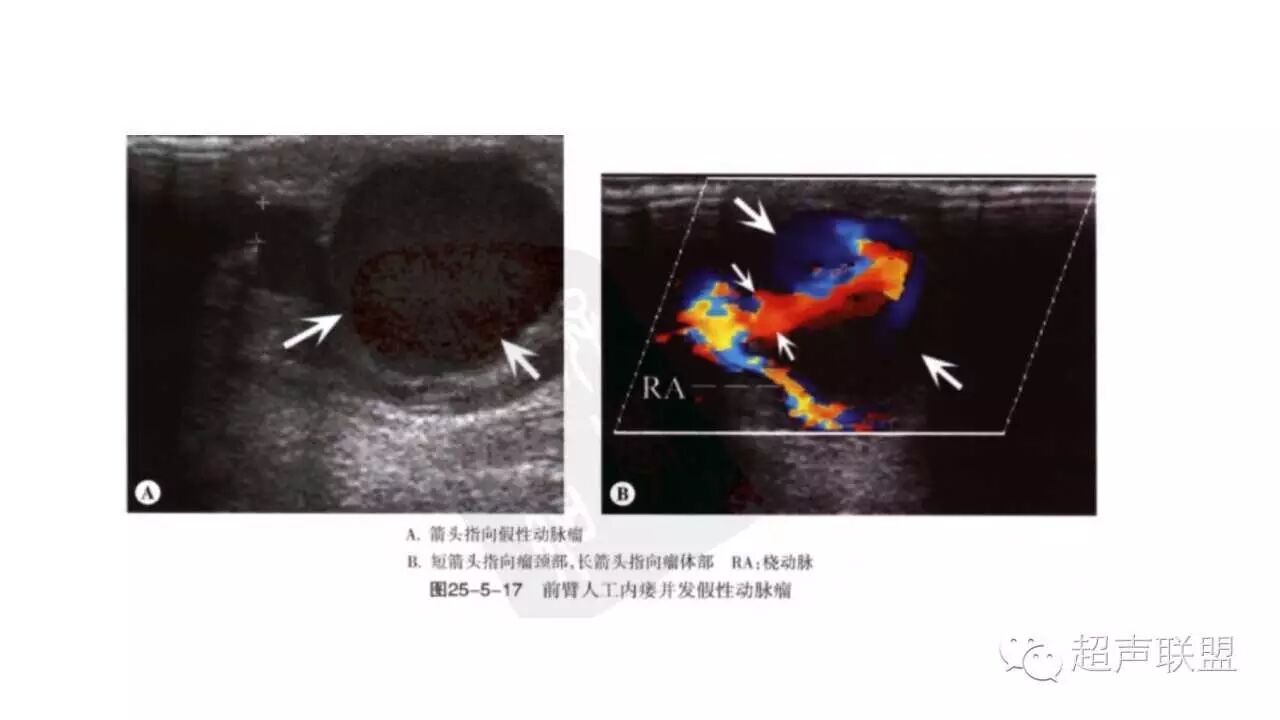

* 病理与声像图:真性动脉瘤,假性动脉瘤,夹层动脉瘤。

真性动脉瘤 | 假性动脉瘤 | |

病因 | 动脉硬化、感染致主动脉瘤样扩张 | 多为外伤致动脉管壁破裂、感染、医源性 |

肿块部位与形态 | 沿动脉纵向分布,呈梭形、囊状、圆柱状 | 位于动脉的一侧或前后,呈囊性或不规则 |

瘤壁结构 | 可分辨动脉管壁三层结构,常有钙化斑块 | 无动脉管壁三层结构,常无钙化斑块 |

瘤壁破裂口 | 无 | 有 |

进口与出口 | 进口与出口分开 | 同一通道 |

双期双向血流 | 无 | 有,血流从同一瘤口进出 |

2、动脉瘤:真性动脉瘤、假性动脉瘤、动脉夹层。